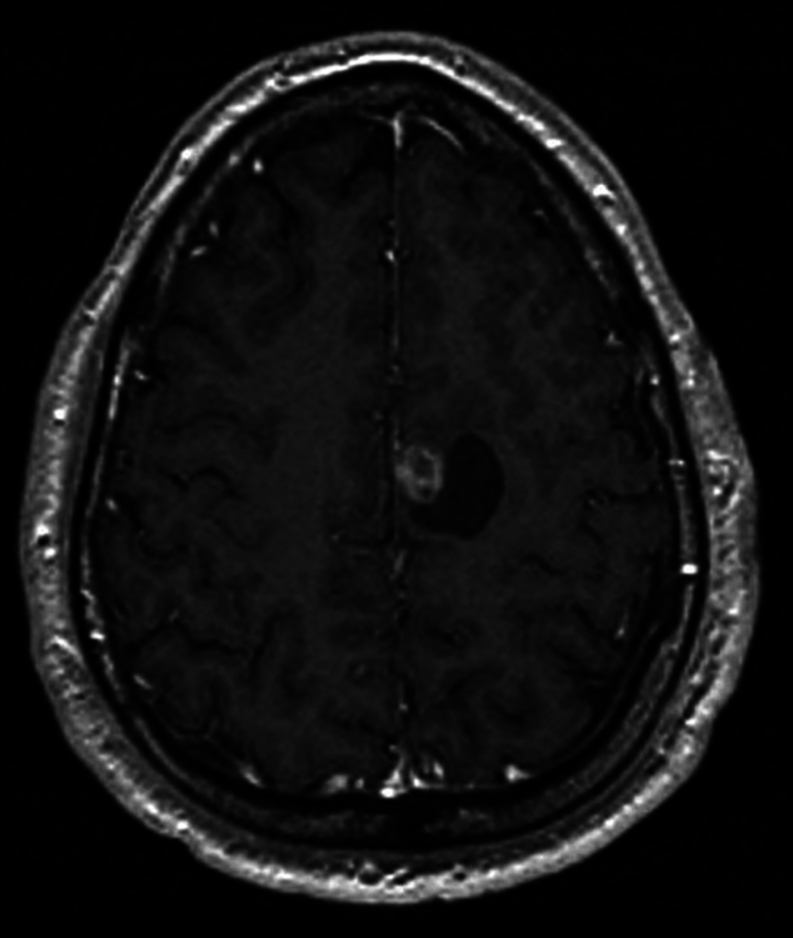

摘要:以脑转移为首发临床表现的甲状腺乳头状癌(PTC)并不多见,而海绵状血管瘤则是常见的脑畸形。我们报告了一例 36 岁男性的病例,他的脑部病变在磁共振成像上模仿了海绵状血管瘤。患者接受了伽玛刀放射外科手术,但 6 个月后出现了神经症状,复查脑部磁共振成像发现肿块明显增大。患者接受了神经外科手术,病变组织学检查显示为甲状腺转移癌。随后进行的PET-CT和颈部超声检查显示,患者右叶结节和同侧淋巴结的存在一致,超声特征均怀疑为恶性肿瘤。患者接受了甲状腺全切除术,并进行了颈部中央和右外侧清扫术,组织学检查证实患者为甲状腺内多灶性 PTC,并伴有淋巴结转移。术后使用了放射性碘,治疗后全身扫描发现甲状腺床内有局灶性摄取,无远处转移或脑残留。确诊两年后,患者健康状况良好,并接受了临床和影像学随访:学习要点:脑海绵状血管瘤是常见的脑血管畸形,通常通过核磁共振成像诊断。尽管核磁共振成像的准确率很高,但该检查并不具有病理诊断性,也不能排除误诊的可能。PTC 的脑转移非常罕见,但也可能与海绵状血管瘤相似。因此,应始终考虑鉴别诊断。

Summary: Brain metastases as the first clinical presentation of a papillary thyroid carcinoma (PTC) are exceptional, while cavernous angiomas are common cerebral malformations. We report the case of a 36-year-old male with an incidental brain lesion mimicking a cavernous angioma on MRI. Gamma knife radiosurgery was performed, but after 6 months, the patient developed neurological symptoms, and a repeat brain MRI revealed a significant increase in the mass. The patient underwent neurosurgery, and the histological examination of the lesion revealed metastatic carcinoma of thyroid origin. PET-CT and neck ultrasound, subsequently performed, were concordant for the presence of a right lobe nodule and ipsilateral lymph nodes, both with ultrasound features suspicious of malignancy. Total thyroidectomy with central and right lateral neck dissection was performed, and histology confirmed an intrathyroidal multifocal PTC with lymph node metastases. Postoperative radioiodine was administered, and focal uptake within the thyroid bed, without distant metastases or brain remnants, was found on the post-therapeutic whole-body scan. At 2 years from diagnosis, the patient is in good health and undergoes clinical and imaging follow-up.

Learning points: Brain cavernous angiomas are common cerebral vascular malformations that are usually diagnosed by MRI. Despite the high accuracy of MRI, the exam is not pathognomonic, and misdiagnosis cannot be excluded. Brain metastases from PTC are very rare; however, they can mimic a cavernous angioma. Therefore, the differential diagnosis should always be considered.